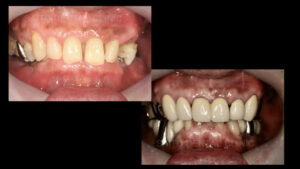

治療前と治療後の状態です ご本人の希望で保険治療でできると所はなるべく保険治療で

治療をし、どうしてもここはしっかり治しておいた方がいいところに治療費用をかけることによって

末長くしっかり噛める状態を作ることができました